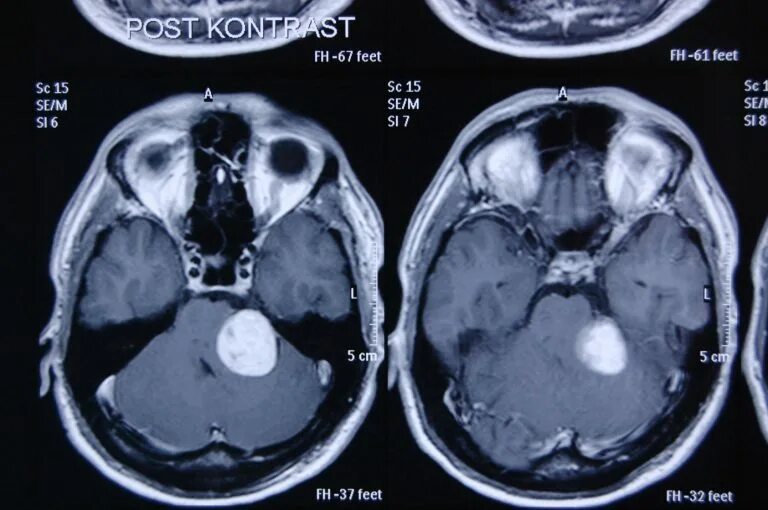

Мрт головного мозга мосто мозжечкового угла